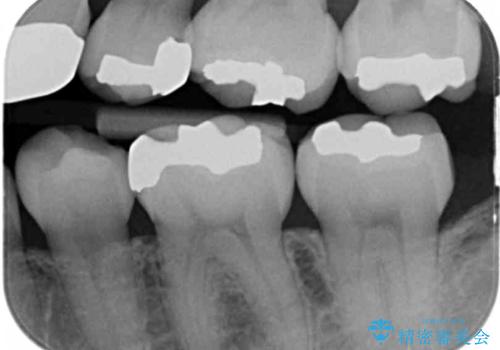

- 銀歯を白くしたいとのことで来院されました。

特に大きな虫歯もなかったため、周りの歯を残しつつセラミックインレーでの修復処置をしていきます。

大きな虫歯さえなければ、銀歯のやり替えは詰め物の周りの歯を保存しつつ修復することができます。